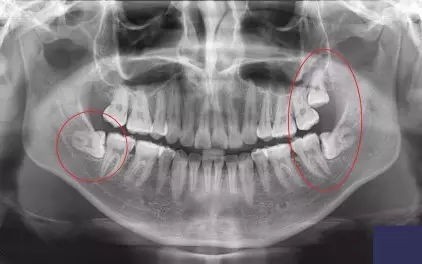

大部分智齿 部分或全部躲在牙龈下 ,肉眼根本看不见,只能 通过X光片看到 。

比如这样:

(肉眼无法看见的 3颗智齿,X光下清清楚楚)